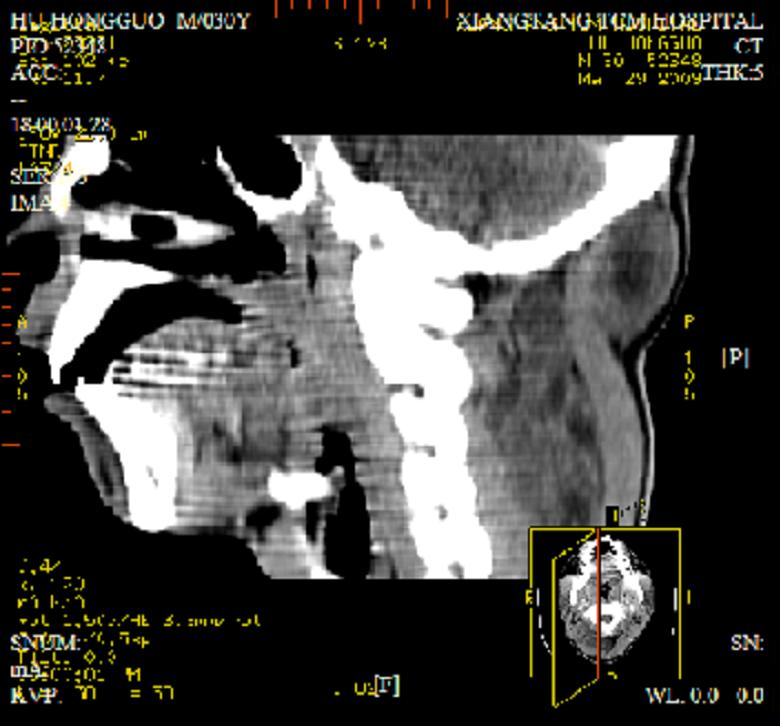

标题: CT19102:颈部肿块

男30y发现肿块3年

多处囊实性肿块,形态欠规则有一定形态,内见点状钙化,以囊变为主,增强后轻度强化,首先考虑神经源性肿瘤如鞘瘤,不除外脉管源性肿瘤如淋巴管瘤(见缝钻及囊性区域太多,如果合并感染完全可以这个影像表现),和海绵状血管瘤,但是血管瘤不太支持因为强化特征和病灶形态不典型.

右侧椎前间隙后部肌间、皮下囊性为主病变,可见分隔和点状钙化,分隔和壁呈轻度环形强化,大部分无强化。形态不规则,有钻缝特点。考虑1 淋巴管瘤合并感染2 血管平滑肌脂肪瘤3 表皮样囊肿4 不除外海绵状血管瘤。